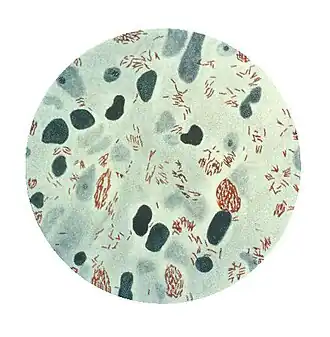

Mycobacterium leprae ou bacilo de Hansen é uma actinobactéria, responsável pela hanseníase (lepra), pertencendo ao gênero Mycobacterium. Possui crescimento extremamente lento quando comparado com outras bactérias.

Bacilos de tamanho médio variando entre 0,3 e 0,5 μm de diâmetro e 4,0 a 7,0 μm de comprimento. A temperatura ótima de crescimento é em torno de 30ºC, motivo pelo qual a bactéria infecta regiões mais frias do corpo (extremidades). Seu cultivo não pode ser realizado em meio de cultura como outras micobactérias, podendo ser inoculada em camundongos ou tatus selvagens.